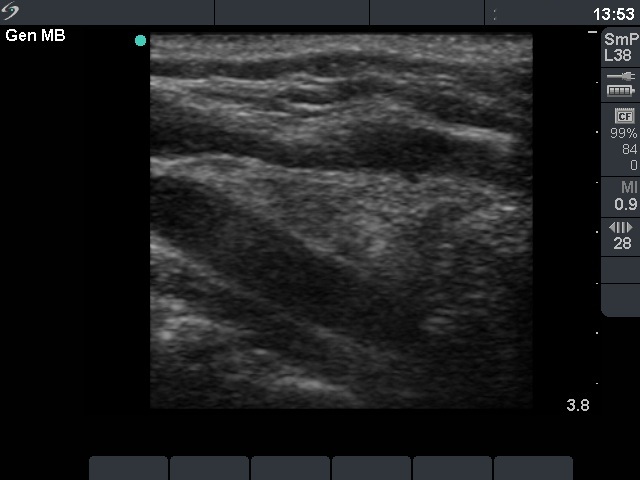

The role of complex diagnosis - oxyphilic lesions - Case 6. (ultrasonographic picture 2)

Right lobe, longitudinal scan. The moderately hypoechogenic areas are signs of the underlying lymphocytic thyroiditis.